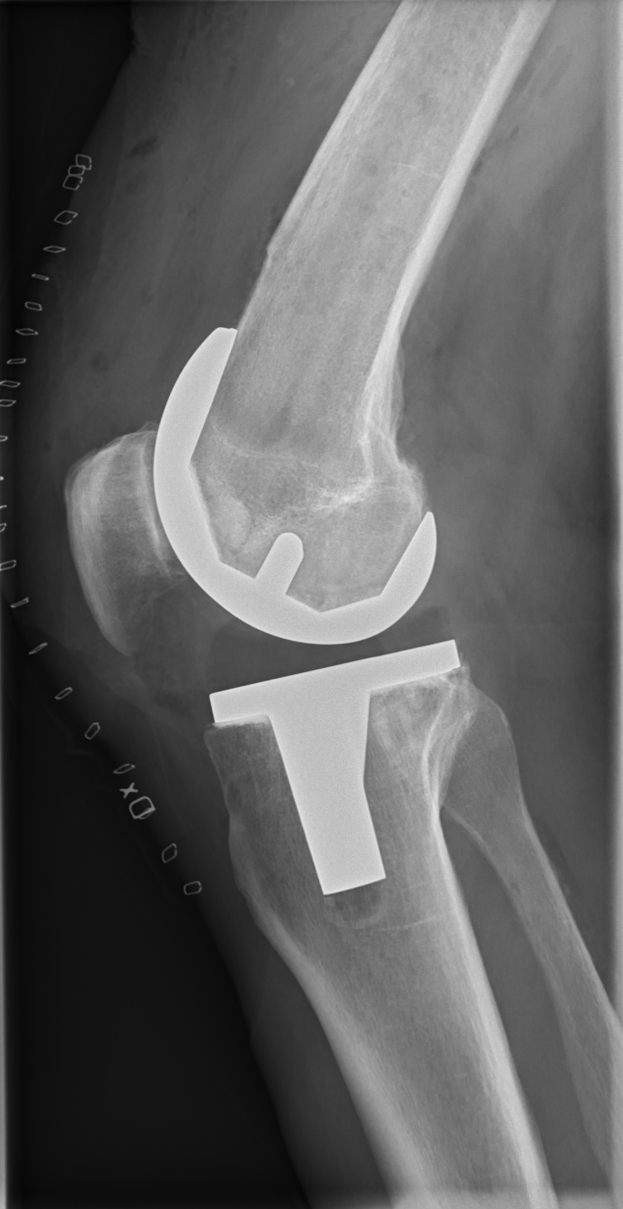

Pöpperl, der 20-jährige Mittelfeldspieler, war erst kürzlich aus der U23 von Schalke in die Zweitligamannschaft aufgerückt. Sein Aufstieg wurde jäh gestoppt, als er sich im Training das vordere Kreuzband riss. Die Verletzung wird ihn für längere Zeit außer Gefecht setzen.